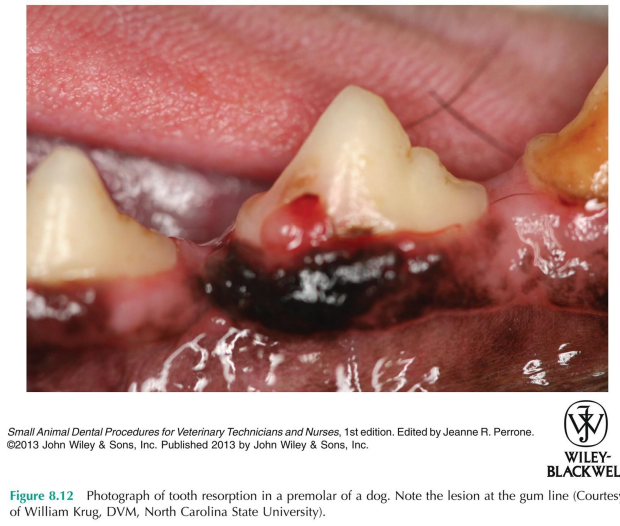

tooth resorption lesion that has reached the crown and granulation tissue as formed a strawberry red uloke